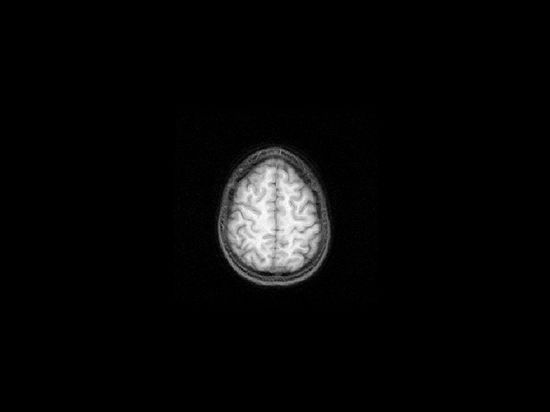

Brain scan technology has been championed as the new frontier for terror interrogations. But Virginia Hughes posits that a "brain-scan lie detector is no more reliable than the polygraph":

[T]he same regions of the brain that light up during lying are the ones that we use for all kinds of high-level cognition and emotion — such as, say, intense anxiety over whether your captors are going to hurt you.

Scientifically, for reasons I described, that’s a waste of time and resources. But some ethicists say that it’s worse. They point to studies showing that non-scientists tend to treat brain scans as more credible and authoritative than other types of information. You can see it plain as day in the intelligence officer’s quote: we only apply intensive interrogation techniques to the ones that show reactions. Or more bluntly: they’re relying on unreliable blips of brain activity to determine which detainees will be tortured.